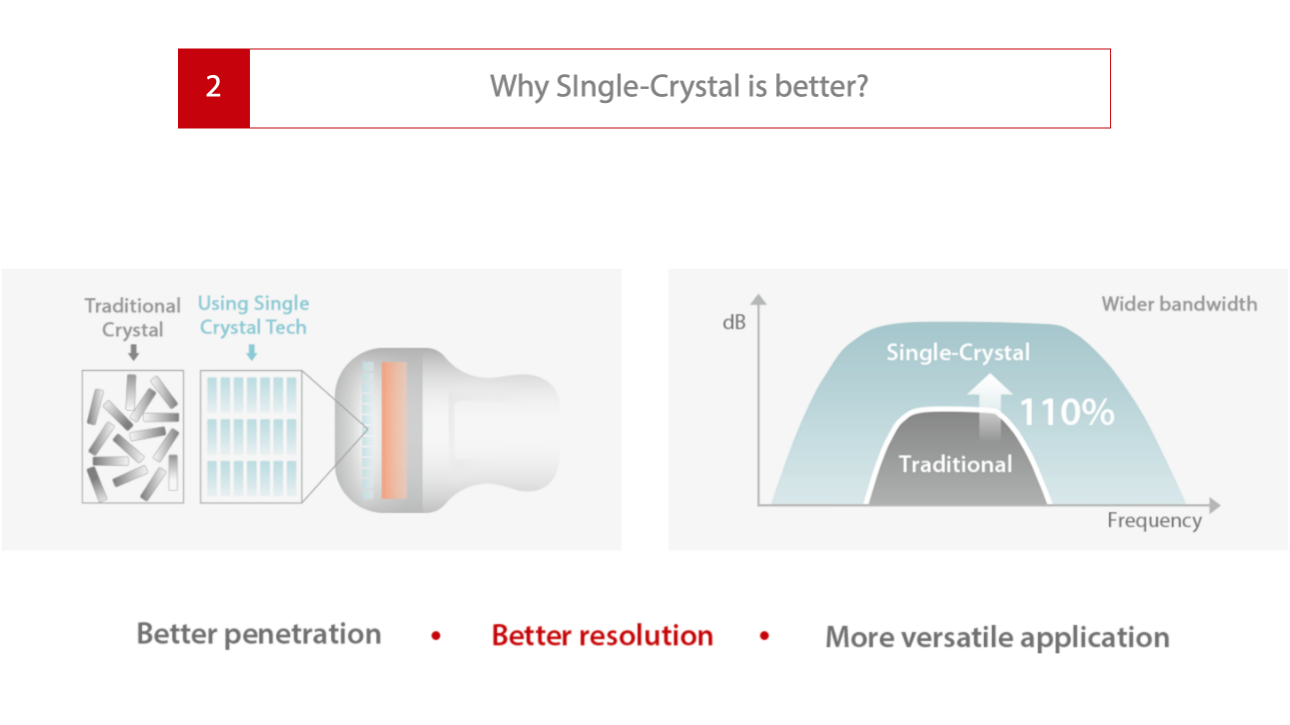

Soins primaires avec Pure Crystal

Niveau Monocristal